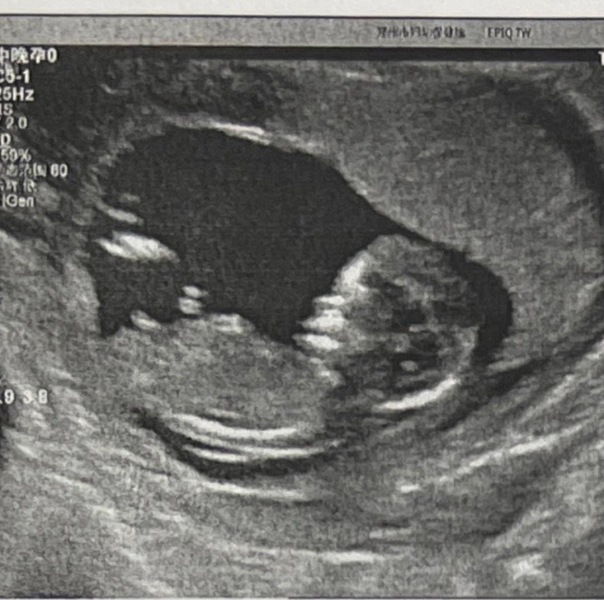

fluffycauliflowers · 01/11/2024 11:48

thank you @lockdownbabyx - this is mine

Nub theory prediction wrong?

lockdownbabyx · 01/11/2024 11:59

I'd say girl based on these, but I am no expert haha xx